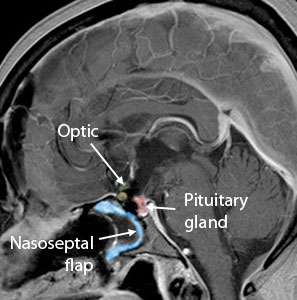

This video shows the endoscopic removal of a craniopharyngioma. The tumor is reached by working over the pituitary gland, taking extreme care to preserve the pituitary stalk. Once the tumor material is removed, the roof of the third ventricle (the deepest area where the tumor was) can be seen. The patient had intact pituitary function and vision after the surgery.

Large craniopharyngioma successfully removed using the Expanded Endonasal Approach.